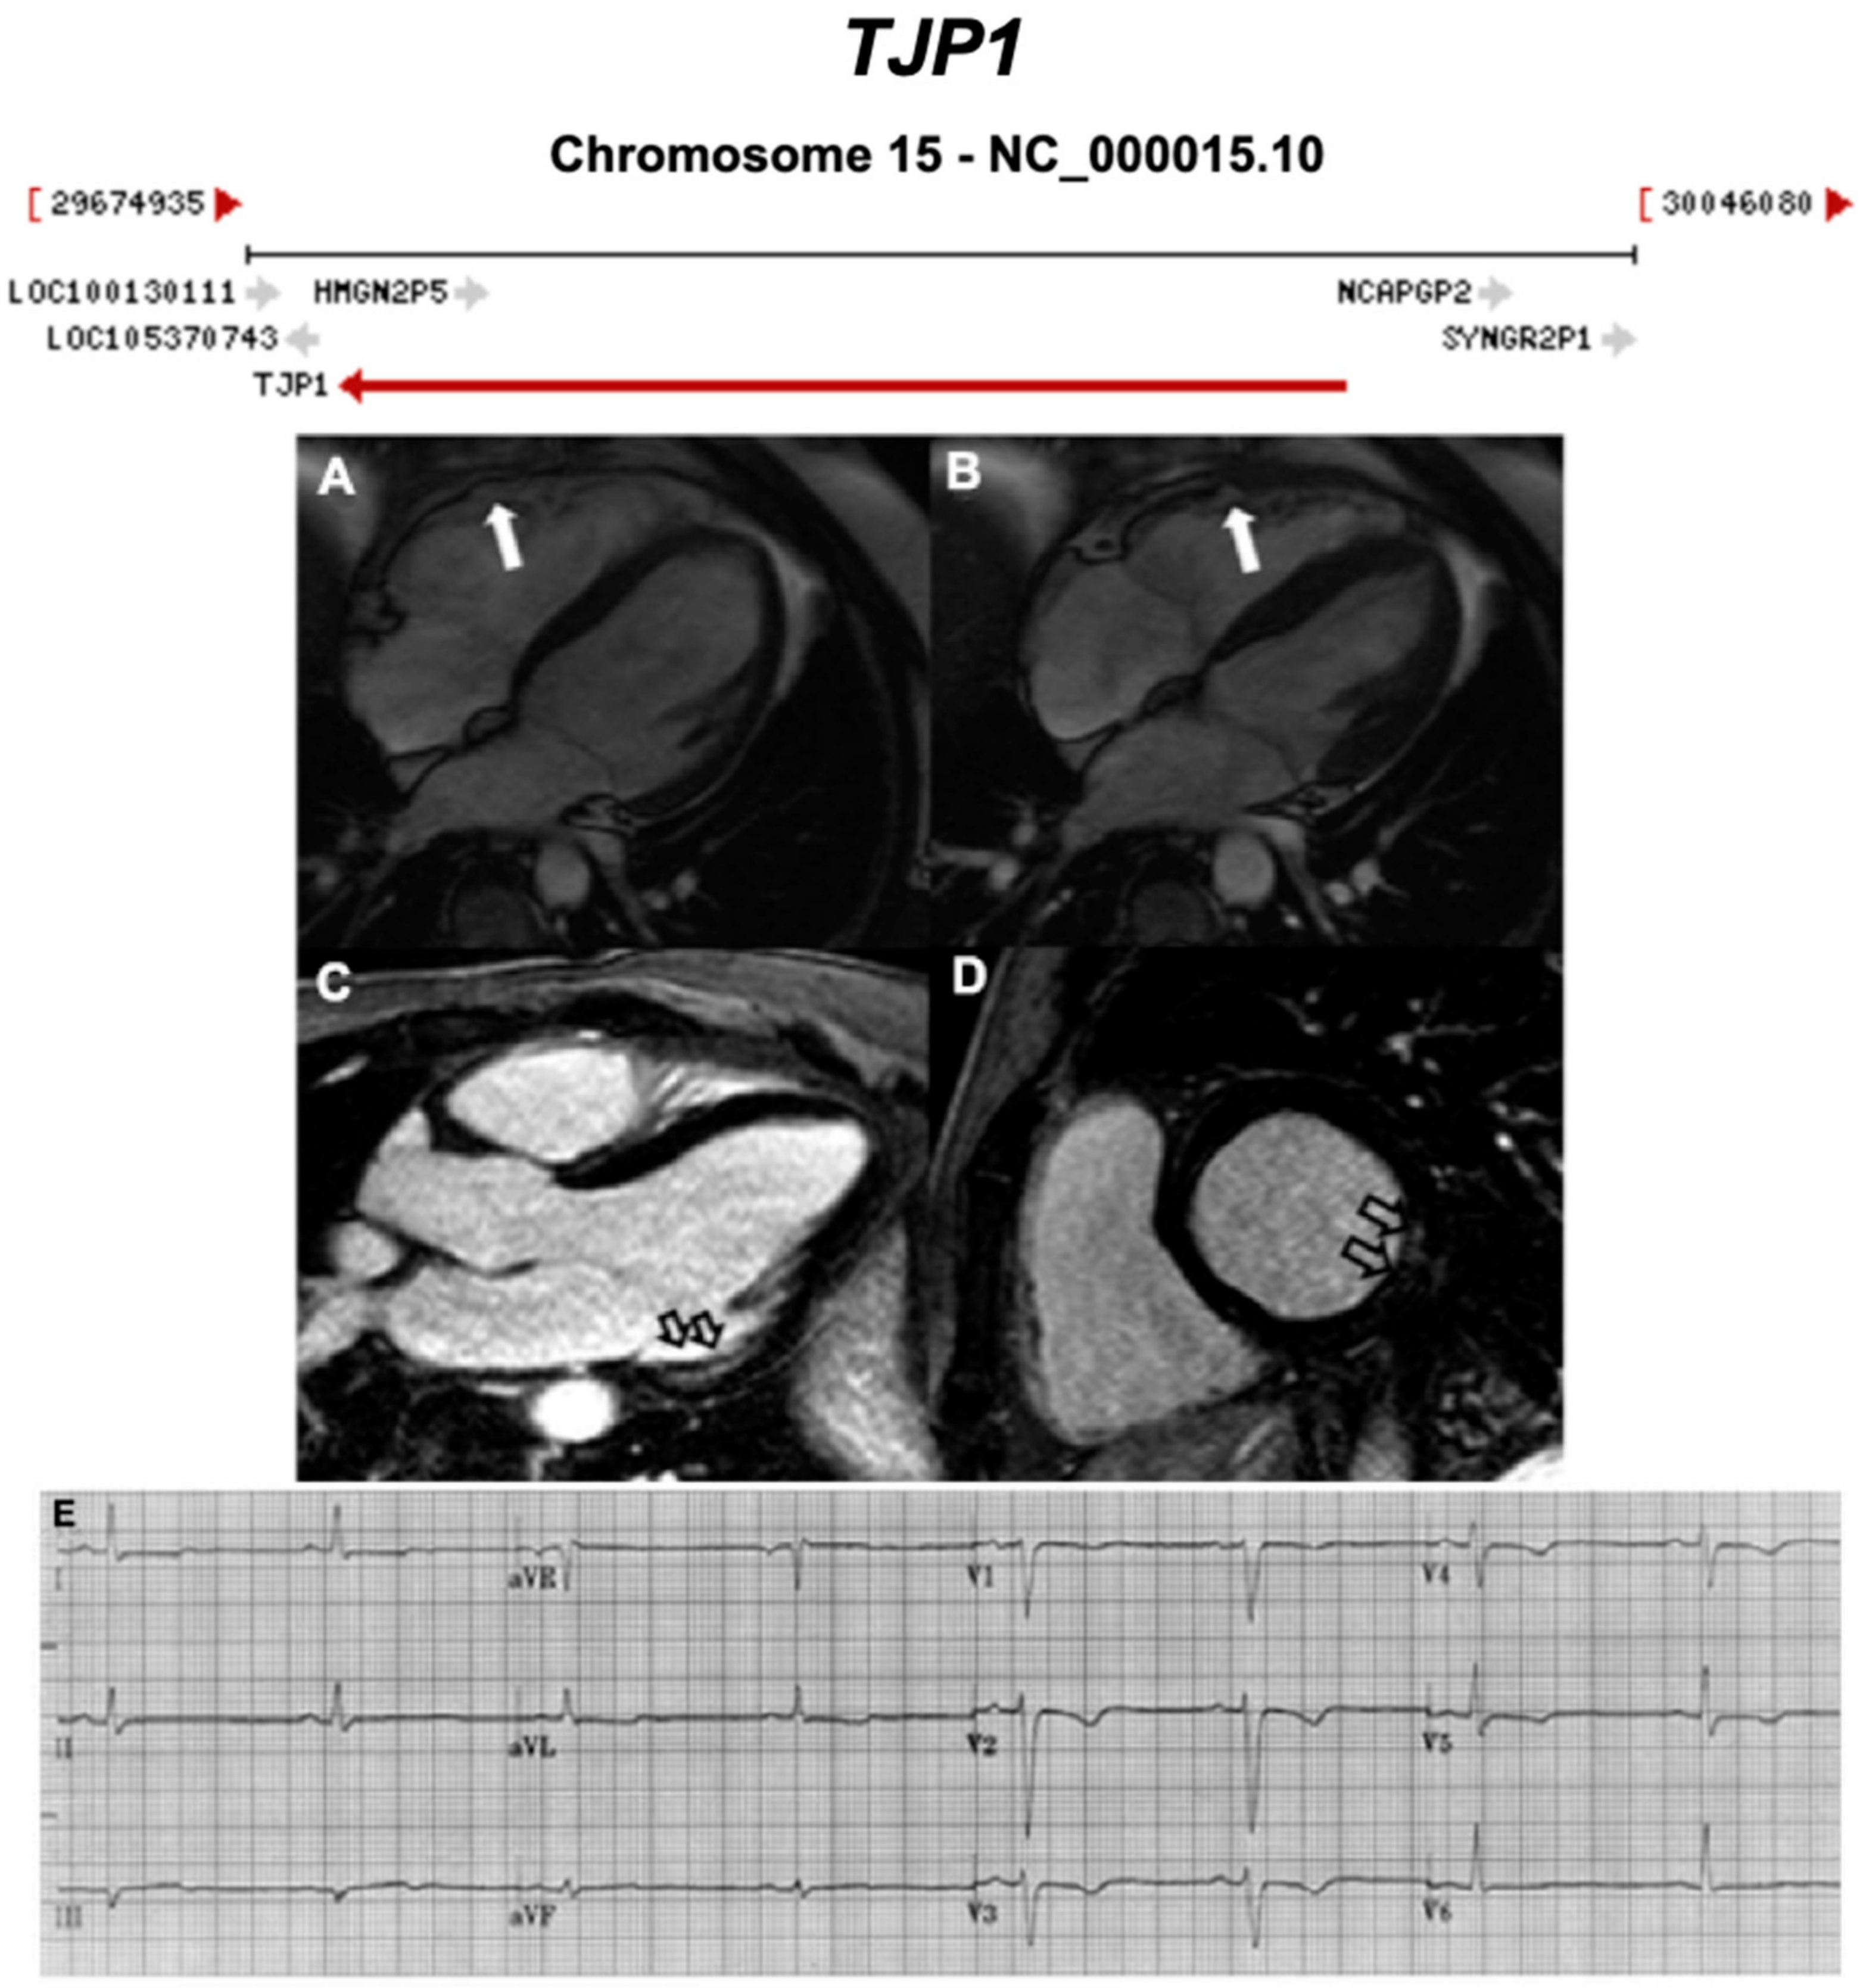

Figure 13.

Exemplar MRI and ECG finding found in ACM patients with TJP1 mutations. (A,B) CMR of a patient with TJP1 p.Tyr669Cys mutation showing right ventricular dilatation (white arrows); (C,D) LGE shows mid-mural fibrosis in the inferior-lateral wall of the left ventricle (empty arrows); (E) 12-lead ECG of the same patient showing shows sinus rhythm, intra-ventricular conduction delay, and T wave inversion in V1 to V5. Reproduced with permission from De Bortoli et al. (2018) [44].